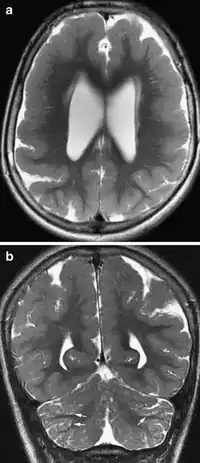

a,b)Bilateral frontoparietal polymicrogyria

Diagnostic criteria for a BFPP patient entails a heterozygous genotype for a deletion of chromosome 16q12.1-q21 region, including GPR56 gene.[11] To date the only gene known to be associated with polymicrogyria is GPR56. Testing for GPR56-related bilateral frontoparietal polymicrogyria is available clinically. Mutations in GPR56 hinders Collagen III, its specific ligand, to bind in a developing brain. To date, a total of fourteen BFPP-associated mutations have been identified, including one deletion, two splicing, and eleven missense mutations. Two mutations in the GPCR proteolytic site (GPS) domain, C346S and W349S, cause a brain malformation through trapping the mutated proteins in the endoplasmic reticulum.[12]

• Radiological findings (MRI) demonstrated symmetric generalized polymicrogyria with decreasing anterior-posterior gradient, most prominent in frontoparietal cortex.[5]

• Numerous gyrus on the cortex

• Small gyri and sulci

• Thin cortex

This child presented with seizures. The coronal true inversion recovery sequence shows thickened and disordered cortex in superior frontal and cingulate gyri bilaterally (arrow). There are small convolutions visible at the corticomedullary junction. The appearance is that of cortical dysplasia, with polymicrogyria more likely than pachygyria due to the small convolutions visible. There are also small foci of grey matter signal in the corpus callosum, deep to the dysplastic cortex (double arrows). These probably represent areas of grey matter heterotopia.

There are different tests or methods used to determine GPR56 expression or visuals of the brain to analyze the specific sections that are affected. These tests for example, using animals such as mice, RNAi, Behavioral assay, Electron microscopy, CT scan, or MRI demonstrate different results that concludes an affected BFPP patient.[16] MRI's reveal either irregularity to the cortical surface suggestive of multiple small folds or an irregular, scalloped appearance of the gray matter-white matter junction.

Neuroimaging The diagnosis of polymicrogyria is typically made by magnetic resonance imaging (MRI) since computed tomography (CT) and other imaging methods generally do not have high enough resolution or adequate contrast to identify the small folds that define the condition. The cerebral cortex often appears abnormally thick as well because the multiple small gyri are fused, infolded, and superimposed in appearance.[5]